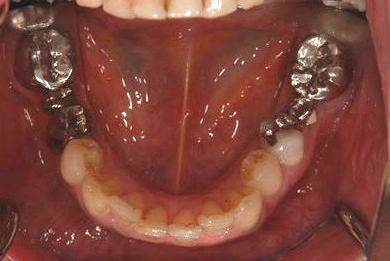

セラミックの症例写真 SHINBI

| 性別/年齢 | 女性 / 41歳 | ||||||||||||||||||||||||||||||||

| 主訴 | 歯が欠けたので、セラミック治療をお願いしたい。 | ||||||||||||||||||||||||||||||||

| 治療方針 | セラミック治療にて、審美的回復を行う。 | ||||||||||||||||||||||||||||||||

| 治療内容 | エンプレスオールセラミッククラウン4本(オールセラミック用土台4本) | ||||||||||||||||||||||||||||||||

| 総治療費 | 408,000円 | ||||||||||||||||||||||||||||||||

| 治療期間 | 4ヶ月 |